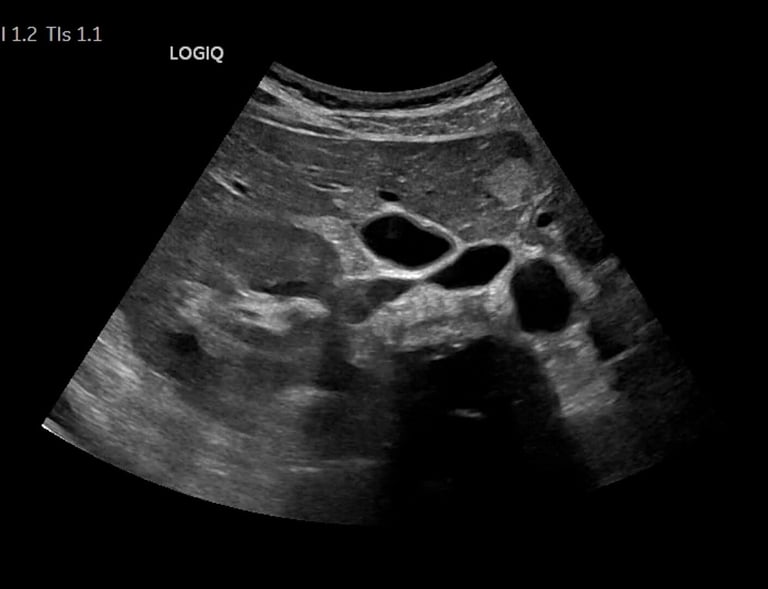

Gallery

Snapshots from our caring ultrasound services